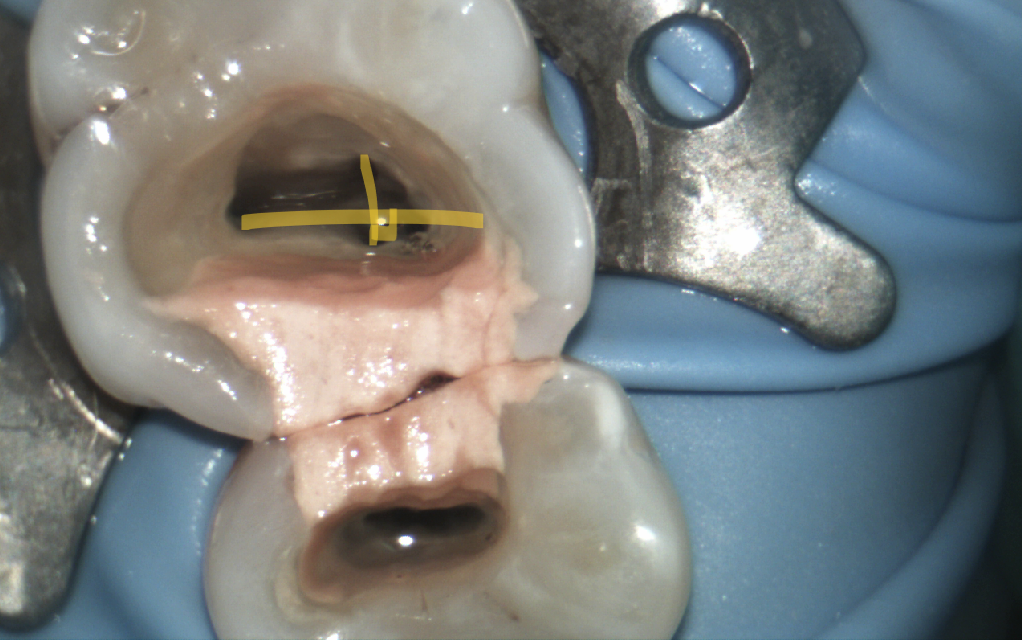

I have found this canal to be extremely challenging to both find and negotiate. I had, once upon a time, thought in theory the MB2 orifice could be located by drawing a line between MB1 and P canal and intersecting it with a perpendicular to the D canal. The MB2 theoretically can be found somewhere along this intersection.

The two yellow perpendicular lines represent the intersection where the MB2 can theoretically be found.